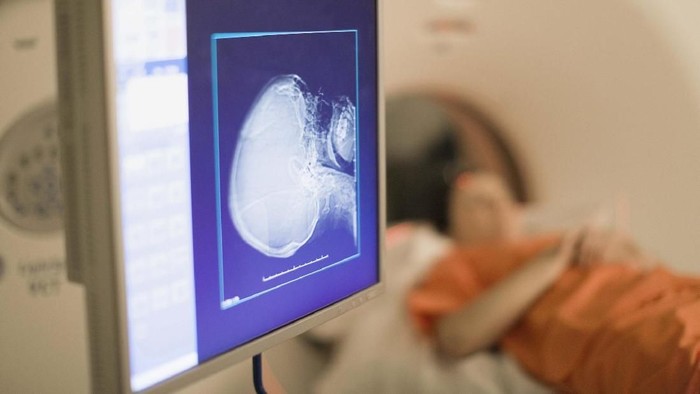

Menurut hasil pemindaian, terlihat ada objek asing yang ternyata adalah mainan seks. Objek itu terseret dari rektum ke rongga dadanya, yang berpotensi merusak organ dan jaringan di sepanjang jalan.